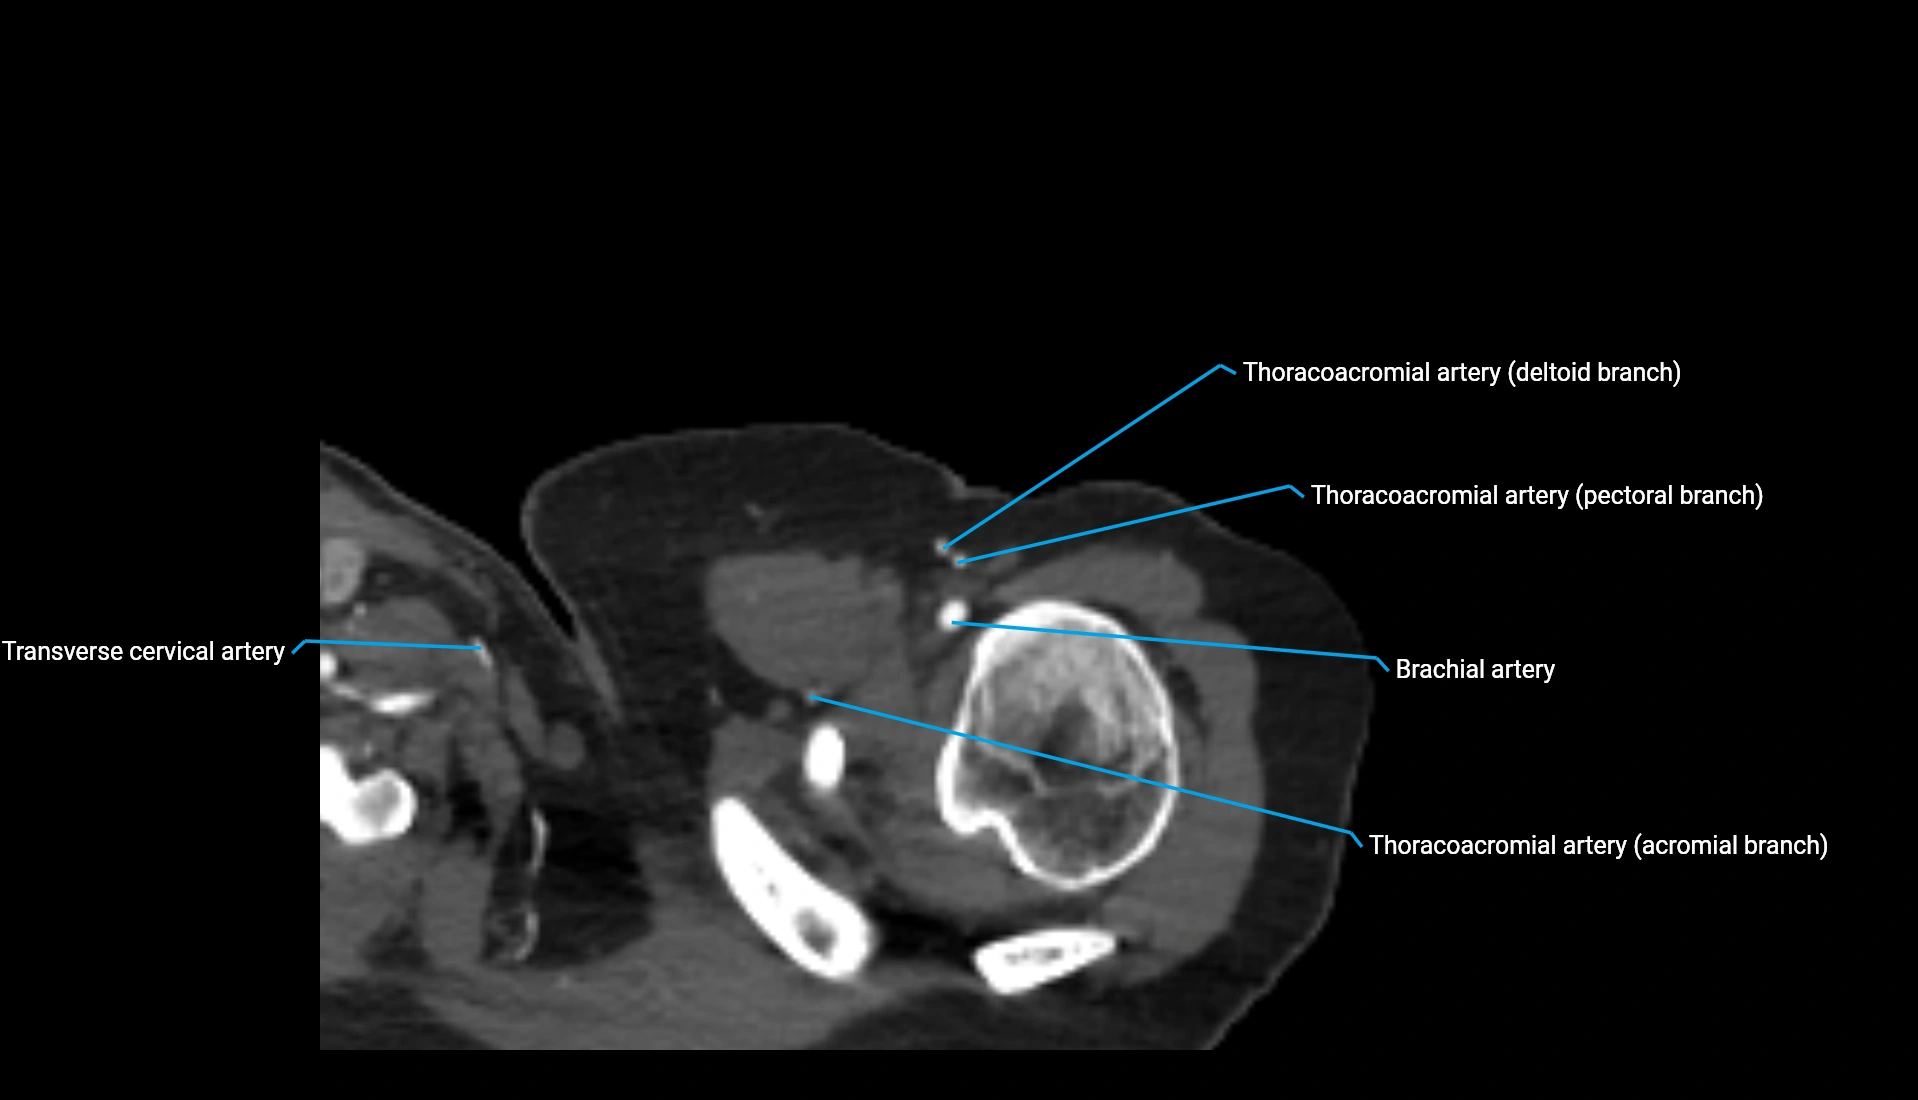

CT Appearance

Non-Contrast CT:

• Cortex: High-density, sharply defined

• Subchondral bone: Dense cancellous matrix

• Articular surface: Smooth concave contour articulating with the capitellum

• Excellent for evaluating bone integrity, alignment, and subtle fractures

Post-Contrast CT:

• Bone: No enhancement

• Joint capsule and synovium: Mild enhancement outlining the joint

• Improves contrast between soft tissues and bony margins

• Useful in detecting subtle joint abnormalities or postoperative changes